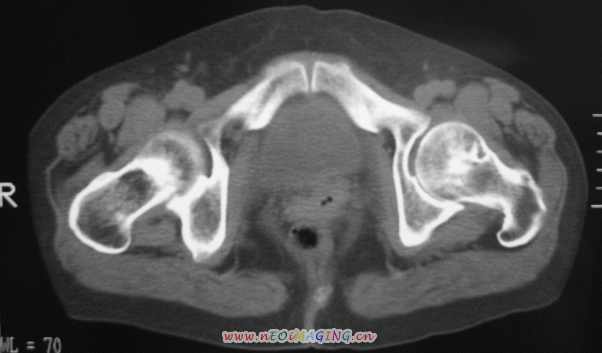

标题: CT11527:女56岁以右输尿管结石入院

女56岁以右输尿管结石入院

病灶位于下腹部盆腔,从子宫与膀胱明显受压后移看,应该来源于盆腹腔的占位,病灶实性部分密度均匀,左侧可见低密度灶,建议增强扫描,考虑:间叶性肿瘤,或硬纤维瘤,输尿管下段结石伴上段输尿管扩张

右侧盆腔占位,考虑来源于卵巢,囊腺瘤可能性大。

右侧输尿管结石。

1)盆腔占位性病变,考虑来源于卵巢,囊腺瘤可能性大。2)右侧输尿管第二狭窄处结石伴梗阻。

今天病人已经手术证实为右附件囊肿,右侧输尿管第二狭窄处结石伴梗阻!!!

[病理诊断] CT11527:右附件囊肿,右侧输尿管结石。